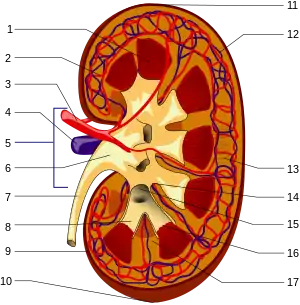

The functional substance, or parenchyma, of the human kidney is divided into two major structures: the outer renal cortex and the inner renal medulla. Grossly, these structures take the shape of eight to 18 cone-shaped renal lobes, each containing renal cortex surrounding a portion of medulla called a renal pyramid.[18] Between the renal pyramids are projections of cortex called renal columns.

The tip, or papilla, of each pyramid empties urine into a minor calyx; minor calyces empty into major calyces, and major calyces empty into the renal pelvis. This becomes the ureter. At the hilum, the ureter and renal vein exit the kidney and the renal artery enters. Hilar fat and lymphatic tissue with lymph nodes surround these structures. The hilar fat is contiguous with a fat-filled cavity called the renal sinus. The renal sinus collectively contains the renal pelvis and calyces and separates these structures from the renal medullary tissue.[19]

Blood supply

The kidneys receive blood from the renal arteries, left and right, which branch directly from the abdominal aorta. The kidneys receive approximately 20–25% of cardiac output in adult human.[18][20][21] Each renal artery branches into segmental arteries, dividing further into interlobar arteries, which penetrate the renal capsule and extend through the renal columns between the renal pyramids. The interlobar arteries then supply blood to the arcuate arteries that run through the boundary of the cortex and the medulla. Each arcuate artery supplies several interlobular arteries that feed into the afferent arterioles that supply the glomeruli.

Blood drains from the kidneys, ultimately into the inferior vena cava. After filtration occurs, the blood moves through a small network of small veins (venules) that converge into interlobular veins. As with the arteriole distribution, the veins follow the same pattern: the interlobular provide blood to the arcuate veins then back to the interlobar veins, which come to form the renal veins which exit the kidney.